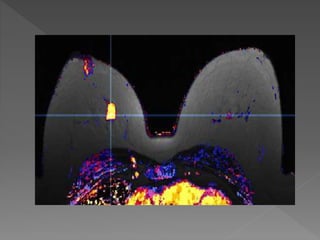

 PAPILAR

 MICROPAPILAR

 CRIBIFORME

 SOLIDO

 COMEDO

LAGIOS/ROSEN/PAGE